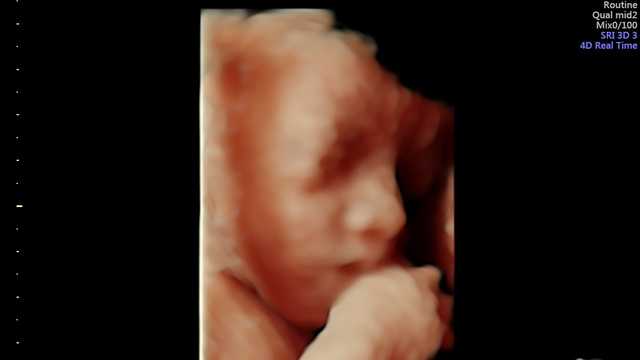

Company photo #1